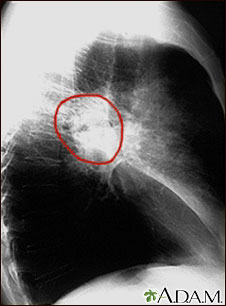

Cáncer de pulmón- Radiografía lateral del tórax

Vista lateral de una radiografía de tórax de un paciente con cáncer en la parte central del pulmón.